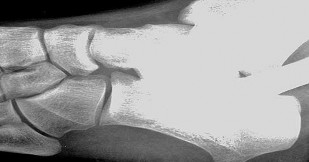

Figures 1a through 1c

Tarsal coalitions occur when primitive mesenchymal cells fail to differentiate and form the

normal articular separations between the tarsal bones of the hindfoot. Overall incidence is difficult to determine because many affected people are minimally symptomatic or asymptomatic. Symptomatic tarsal coalitions typically present in adolescents as a painful flatfoot; however, there are a number of possible presentations, and occasionally symptoms do not appear until adulthood. Most tarsal coalitions are between the calcaneus and the navicular (CN) and the talus and the calcaneus (TC). Although most TC coalitions are across the middle facet, posterior facet coalitions do occur. Plain radiographic evaluation of suspected tarsal coalition is the mainstay for diagnosis. However, coalitions can be bony or fibrous, and making the diagnosis can be difficult. The addition of CT images to distinguish bony definition and MR images to decipher soft tissue can aid in diagnostics. Bony coalitions appear as definite bony bridging between the bones, while fibrous coalitions are suspected when distortion of the bony anatomy is seen. Bony coalitions are best seen on the oblique view (CN) and Harris axial view (TC). There are a number of secondary signs such as the anteater (AE) sign (elongation of the anterior process of the calcaneus as it extends to the navicular as seen on the lateral view [CN]). talar beaking (traction spur of the talar neck thought to result from abnormal stresses as seen on the lateral view [both CN and TN]), and the “C” sign (a continuous cortical contour from the medial talus to the sustentaculum tali [ST]) as seen on the lateral view (TC). A number of newer signs are not as well known, such as a broad mediolateral dimension of the navicular on the anteroposterior (AP) view (the

navicular is wider than the talar head [CN]), nonvisualization of the middle facet on the lateral view (TC), the brick sign (a normal ST is flat, but a distorted ST is enlarged and curved [CN]), and a tapered lateral navicular bone as seen on the AP view (the medial navicular [CN] is much thicker than the lateral navicular).

Figure 1a shows talar beaking (TB), an AE, and an open middle facet (MF). Figure 1b shows a wide navicular (WN), and Figure 1c shows an abnormal articulation between the calcaneus and the navicular, all consistent with a CN coalition.